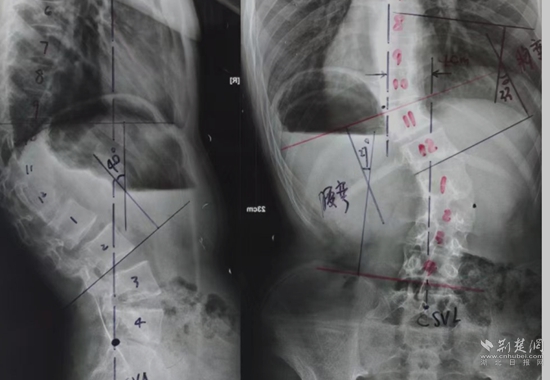

全脊柱X光檢查。通訊員 供圖

余國(guó)慶醫(yī)生檢查后發(fā)現(xiàn),這名患者全身皮膚長(zhǎng)滿咖啡色的斑塊和瘤狀的突起,身體極為消瘦,骨架突出后可以看到明顯的駝背、剃刀背及側(cè)彎畸形。結(jié)合隨后的全脊柱X光檢查,確診這是一例少見(jiàn)的神經(jīng)纖維瘤病性脊柱側(cè)后凸畸形患者。余醫(yī)生當(dāng)即將這名患者收住院治療。